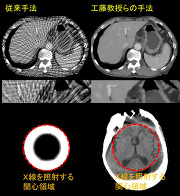

(対象となった研究成果の中から低被曝を実現する「スパースビューCT」と「インテリアCT」の画像再構成例(上段:通常の約1/40に相当する僅か40方向のスパースビューCT投影データからの腹部CT画像の再構成,下段:検査の関心領域のみにX線を照射したインテリアCT投影データからの頭部CT画像の再構成))